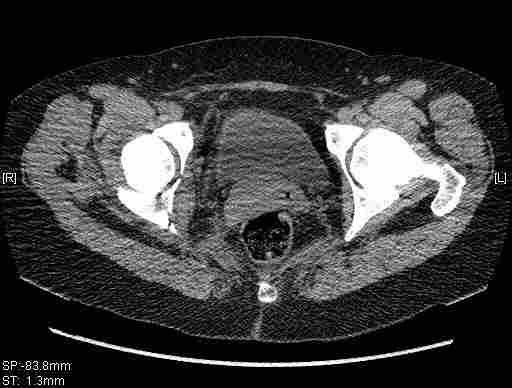

Удалось сегодня вывести пациентку в соседнюю больницу, где есть кт. Срезы сделаны только горизонтальные.

Приветствую,Антон.Рункова рядом нет,но после полученных данных КТ,обсуждали совместно.Итог обсуждения-развернутый ответ дать не получится,т.к.срезы выбраны не информативные.Если ориентироваться на данные 3D,то ,ИМХО,можно лечить на вытяжении.

Спасибо, Салават и коллеги. Насколько я понял,нужны срезы в сагитальной и фронтальной плоскостях?